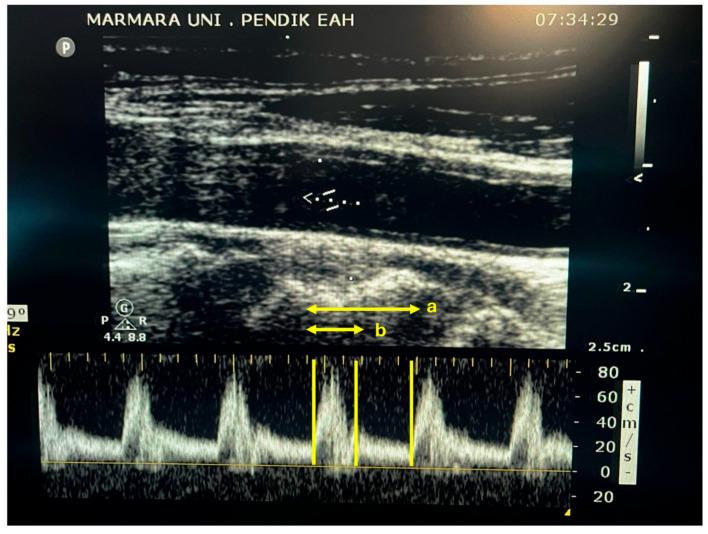

The Reliability of Carotid Artery Doppler Ultrasonography Indices in Predicting Fluid Responsiveness during Surgery for Geriatric Patients: A Prospective, Observational Study.

Elderly patients undergoing major surgery under general anesthesia were included. Measurements of common carotid artery diameter, velocity time integral, and systolic flow time (FT) were performed before and after a fluid challenge. FTc and carotid blood flow (CBF) were subsequently calculated.

The median change in carotid diameter was significantly higher in the fluid-responder (R) compared to the non-responder (NR) (6.51% vs. 0.65%, = 0.049). The median change in CBF was notably higher in R compared to NR (30.04% vs. 9.72%, = 0.024). Prior to the fluid challenge, systolic FT was significantly shorter in R than NR (285 ms vs. 315 ms, = 0.027), but after the fluid challenge, these measurements became comparable among the groups. The change in systolic FT was higher in R (15.38% vs. 7.49%, = 0.027). FTc and the change in FTc exhibited similarities among the groups at all study time points. Receiver operating characteristic analysis demonstrated an area under the curve of 0.682 (95% CI: 0.509-0.855, = 0.039) for carotid diameter, 0.710 (95% CI: 0.547-0.872, = 0.011) for CBF, 0.706 (95% CI: 0.540-0.872, = 0.015) for systolic FT, and 0.580 (95% CI = 0.389-0.770, = 0.413) for FTc.

In geriatric patients, potential endothelial changes in the carotid artery may influence the dynamic markers of fluid responsiveness. Despite the demonstrated effectiveness of FTc in predicting fluid responsiveness in the general population, this study underscores the limited reliability of carotid Doppler ultrasonography indices for prediction in a geriatric patient population.